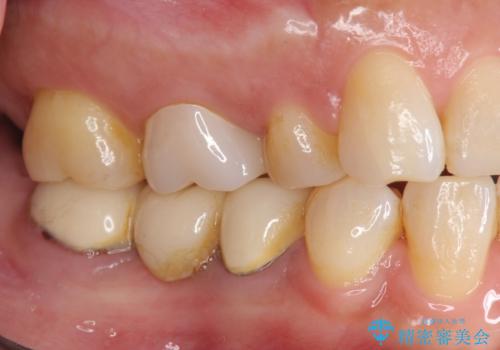

「ブリッジのところで噛むと痛い」 神経組織が原因の咬合痛

- 「以前治療して装着した右下のブリッジの部分で噛むと痛い、何もしなくても痛い」、と治療を希望され来院されました。

X線写真より歯の神経組織が壊死し、根尖周囲に病変を作り透過像を呈している状態でした。

咬合痛の原因となっている右下第2大臼歯の根幹治療を行ったのち、強度に優れるフルジルコニアクラウンによる咬合機能回復を計画します。